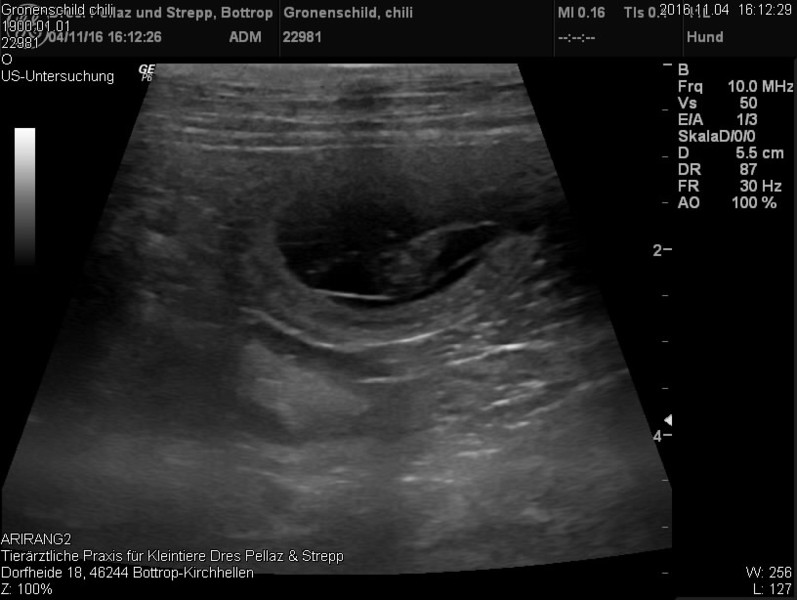

D-Wurf, voraussichtliche Geburt Winter 2016. Nachfolgend die Bilder von der Ultraschalluntersuchung.

Ultraschallbilder vom 04.11.2015.